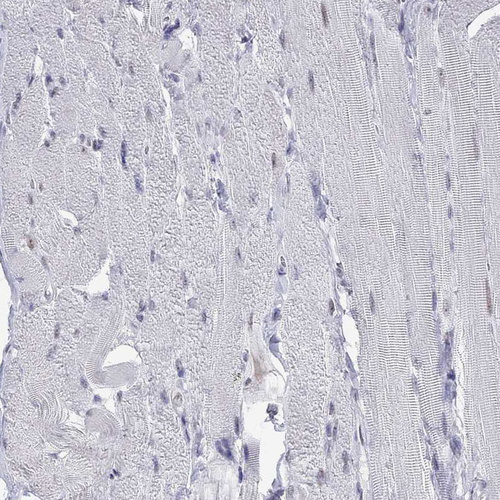

Immunohistochemistry analysis in human testis and pancreas tissues using HPA035531 antibody. Corresponding PPM1G RNA-seq data are presented for the same tissues.